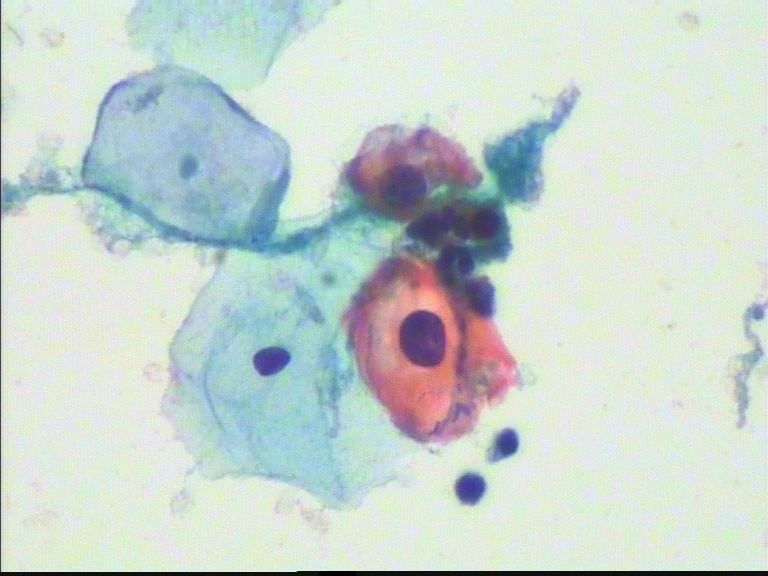

宫颈重糜,42岁。

参考诊断

HSIL